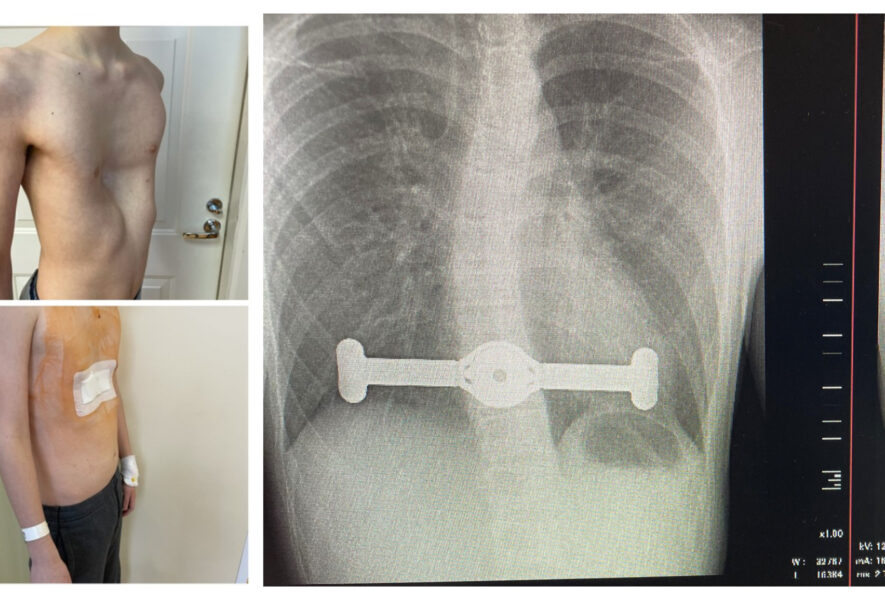

Rentgeno nuotr. Krūtinės ląstos įdubimo operacija

Santaros klinikų Vaikų ortopedijos ir traumatologijos skyriaus vedėjas ortopedas traumatologas Giedrius Bernotavičius pirmasis Baltijos šalyse dviem keturiolikmečiams atliko įdubos krūtinės korekciją naujuoju būdu.

Gydytojas džiaugiasi, kad procedūra naujaisiais implantais – plokštelėmis – yra ne tik saugesnė, bet ir mažai invazyvi, todėl gerokai paprastesnė. Procedūra trunka iki valandos, gijimas nepasižymi dideliu skausmu ar ilga reabilitacija: iš ligoninės pacientai išleidžiami po paros ar dviejų ir greitai sugrįžta į kasdienį gyvenimą.